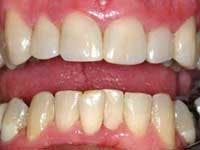

This amount of treatment may be more than the patient can afford in one year, even when using any third–party benefit that is present. If so, segment the first portion into more piecemeal treatment, doing only the mandatory therapy first. As an example, if a significant amount of therapy has been needed before treating the six anterior teeth, these teeth may be treated in the second year. However, I prefer treating the upper anterior teeth in the first year if possible. Often, the anterior teeth can be treated conservatively rather than using crowns, to provide even more motivation for the patient to continue with the therapy. (See Fig. 4.)